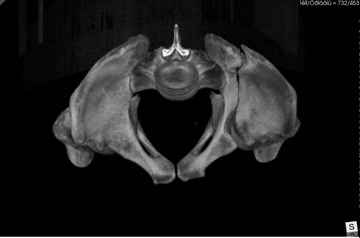

Добрый вечер уважаемые коллеги. Госпитализирован пациент с переломом таза 9-ти месячной давности (лечился где-то в районе консервативно). Помогите определиться с оптимальным вариантом хирургического доступа, фиксации.

Пациенту чуть больше сорока лет, работал в МЧС, после ДТП лечился по месту жительства консервативно. Жалобы пациента на постоянные боли в месте перелома, ощущение подвижности в месте перелома при ходьбе. Передвигается без дополнительной опоры, хромота не щадящая. Клинически отчетливо определяется патологическая подвижность крыла левой подвздошной кости. R-ммы не высылаю, сразу 3-D, если не хватит дошлю снимки.